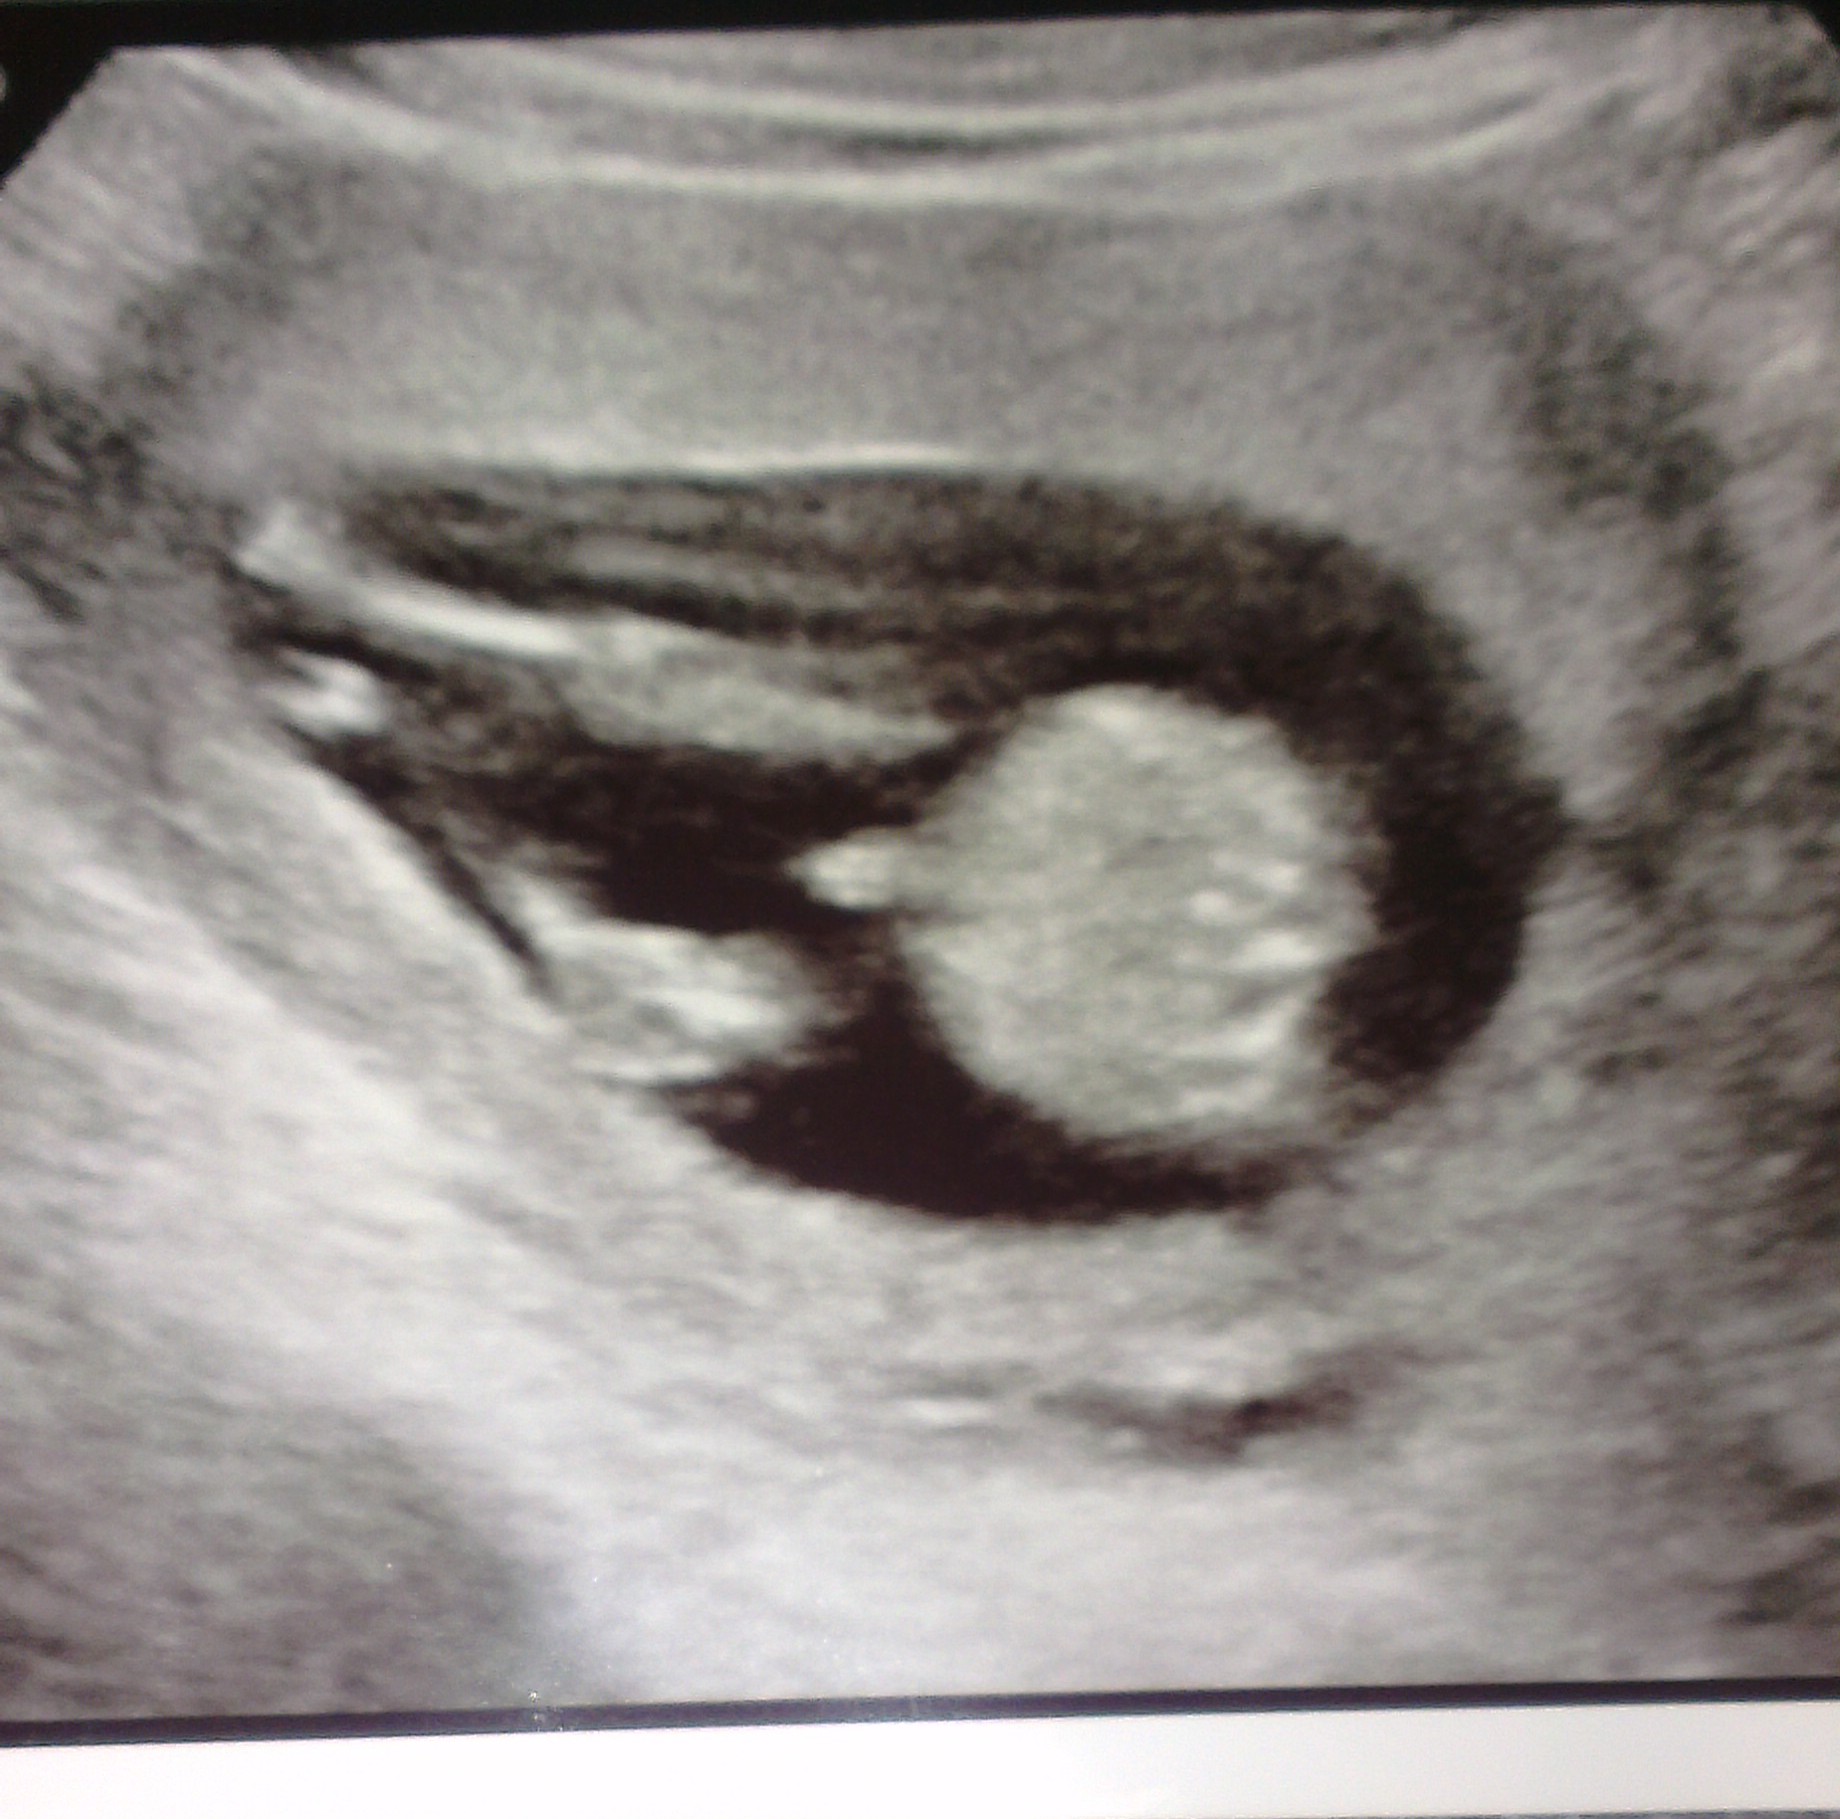

13w 6 day NT scan. Tech said she thought it was a boy. Of course that was before either of these 2 pics. Am I seeing cord or penis here?Thanks in advance!! Attachment 13823 Attachment 13822

The first pic looks like the penis but the second I think is the cord

Thank you all for the responses! I just kept looking at the pics and thinking it could go either way! The first picture is the one I think looks the most penis-y. I'm not really even sure what I'm looking at in the 2nd pic. I assume legs and belly.

I think it's a cord and pretty sure you can only tell from a potty shot. (If it's not the cord, where IS the cord? it should be on top of the nub, right?) Post it on the ultrasound board of babycenter and ask for turtle!